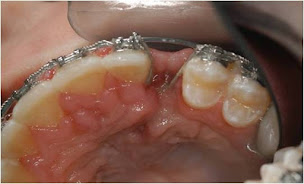

Galerie Photos